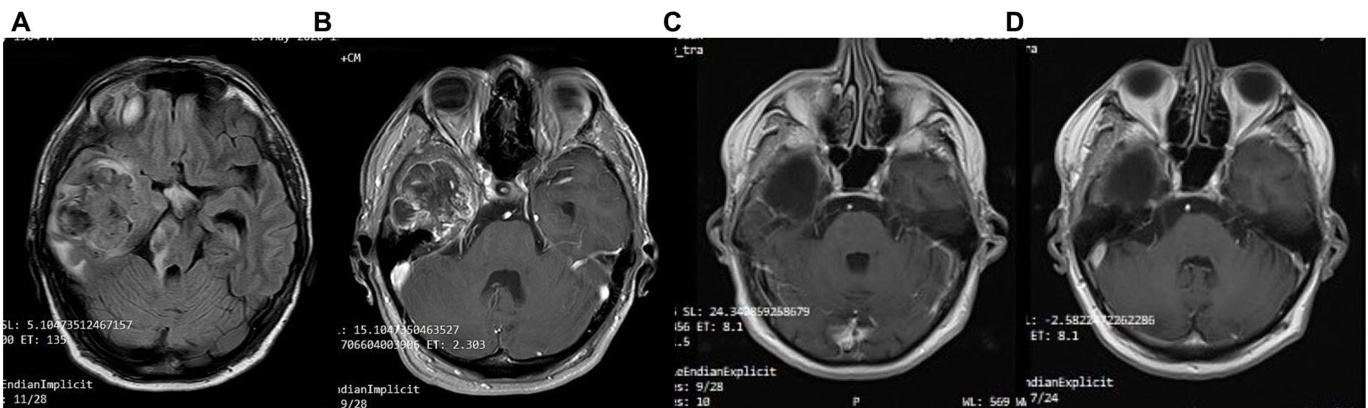

Patient 2 is a 59-year-old male. He is a primary school teacher in very good general condition, with a lean and athletic build (marathon runner). On 23/05/2020, at the age of 56, he was hospitalized due to persistent headache and a sudden onset of left hemi pares is, confusion, and vomiting. Brain CT showed a space-occupying right parietal– temporal lesion with solid and cystic elements and peripheral enhancement, as well as large perifocal edema with midline shift of $12\mathrm{mm}$ . A subsequent brain MRI (Figure 5) showed a large heterogeneous mass in the right tempor o parietal area, $53\mathrm{mm}$ in diameter, with hemorrhagic and necrotic elements and peripheral gadolinium enhancement, surrounded by extensive vasogenic edema. These radiological features were highly suggestive for GBM. On $05/06/2020$ , he underwent a total resection of the tumor through a right temporal craniotomy. He was discharged with le vet i race tam $1{,}000~\mathrm{mg}$ $\times2/$ day and methyl pre dni sol one per os in gradual tapering. His to logical examination (Figure 4) confirmed GBM, immuno his to chemically negative for IDH-1 mutation (GBM NOS). On 28/06/2020 he suffered a lower extremity deep vein thrombosis (DVT) and was placed on a therapeutic dose of heparin for 8 months. The patient followed 30 cycles of radiation (21/7/2020–31/8/2020) and was placed on temozolomide $150:\mathrm{mg/m}^{2}$ , 5 days/month, which continues until the present day. A classic ketogenic diet was implemented on 19/8/2020 with a ketogenic ratio $>2{:}1$ and a total daily calorie intake of $2,150\mathrm{kcal}$ (Table 3).

患者2为59岁男性,小学教师,总体健康状况良好,体型精瘦且运动型(马拉松跑者)。2020年5月23日(56岁时)因持续头痛伴突发左侧偏瘫、意识混乱及呕吐入院。脑部CT显示右顶颞叶占位性病变,含实性与囊性成分及周边强化,伴大面积瘤周水肿(中线移位达12mm)。后续脑部MRI(图5)显示右颞顶区存在53mm直径的异质性肿块,含出血坏死成分及周边钆剂强化,周围伴广泛血管源性水肿,影像学特征高度提示胶质母细胞瘤(GBM)。2020年6月5日行右颞开颅肿瘤全切术,出院时服用左乙拉西坦1,000mg(每日两次)并逐步减量口服甲泼尼龙。组织学检查(图4)确诊为IDH-1突变阴性的GBM(非特指型)。2020年6月28日出现下肢深静脉血栓(DVT),接受治疗剂量肝素治疗8个月。患者完成30次放疗(2020年7月21日–8月31日)后持续服用替莫唑胺(150mg/m²,每月5天)至今。2020年8月19日开始实施经典生酮饮食(生酮比>2:1,每日总热量摄入2,150kcal)(表3)。

The patient achieved satisfactory ketosis as early as the 1st week of diet initiation, with blood ketone levels of $2.9{-}5~\mathrm{mmol/L}$ and morning blood sugar of approximately $72{-}75\mathrm{mg/dL}$ . Nutritional ketosis is maintained until today. Close monitoring with serial MRIs shows no evidence of GBM recurrence throughout the observation period of 43 months (Figure 5). The patient is fully ambulatory, still working as a primary school teacher, with no imaging or clinical signs of disease activity. His most recent ECOG grade is 0.

患者在开始饮食治疗的第1周就达到了理想的酮症状态,血酮水平为$2.9{-}5~\mathrm{mmol/L}$,晨间血糖约为$72{-}75\mathrm{mg/dL}$。营养性酮症状态持续至今。通过连续MRI密切监测显示,在43个月的观察期内未出现胶质母细胞瘤(GBM)复发迹象(图5)。患者行动完全自如,仍担任小学教师工作,影像学及临床表现均无疾病活动征象。其最近一次ECOG评分为0级。

FIGURE 5 Patient 2: (A) pre-operative brain MRI (T2/FLAIR) (B) pre-operative brain MRI (T1 with contrast) (C) 20-month follow-up brain MRI (T1 with contrast) (D) 40-month follow-up brain MRI (T1 with contrast).

图 5 患者 2: (A) 术前脑部 MRI (T2/FLAIR) (B) 术前脑部 MRI (T1 增强) (C) 20 个月随访脑部 MRI (T1 增强) (D) 40 个月随访脑部 MRI (T1 增强)。